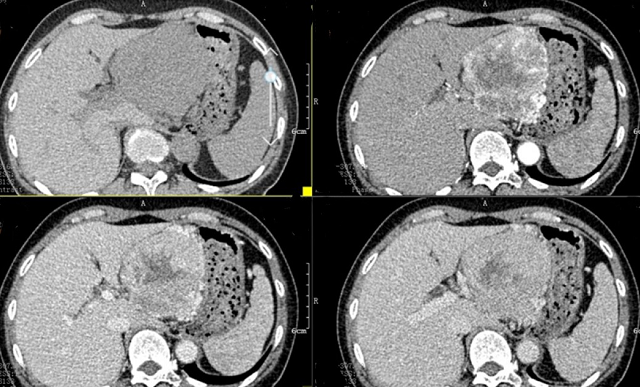

上腹部CT顯示胰腺巨大腫瘤

入院后,根據(jù)王女士病情,曹利平教授及其團(tuán)隊(duì)為她制定一套詳盡的術(shù)前檢查和治療方案。首先,安排做上腹部增強(qiáng)CT,并建議其先穿刺活檢明確病理。

“CT表現(xiàn)符合胰腺神經(jīng)內(nèi)分泌腫瘤,穿刺也證實(shí)無誤,但是瘤體實(shí)在太大,直徑約12cm左右,腹腔內(nèi)的門靜脈、腸系膜上靜脈、脾靜脈以及腹腔干這些重要血管統(tǒng)統(tǒng)包繞進(jìn)去了,且與周圍結(jié)腸系膜也有累及。”

曹利平教授帶著團(tuán)隊(duì)成員逐一分析,隱藏在瘤體附近的血管就像埋在炸彈旁的導(dǎo)火索,稍有不慎,便會(huì)引爆這顆瘤體炸彈,要想把腫瘤完整切除,更是難上加難。